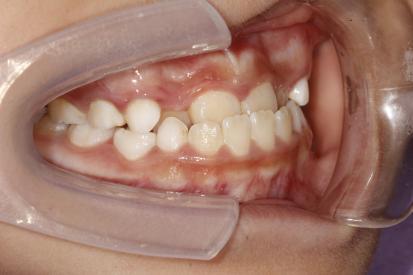

案例四:

治疗前

治疗后